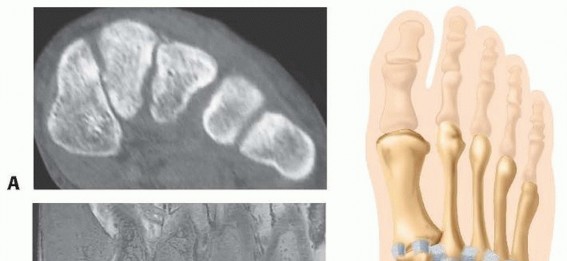

Chapter 37 Open Reduction and Internal Fixation of Lisfranc Injury Michael P. Clare Roy W. Sanders DEFINITION…